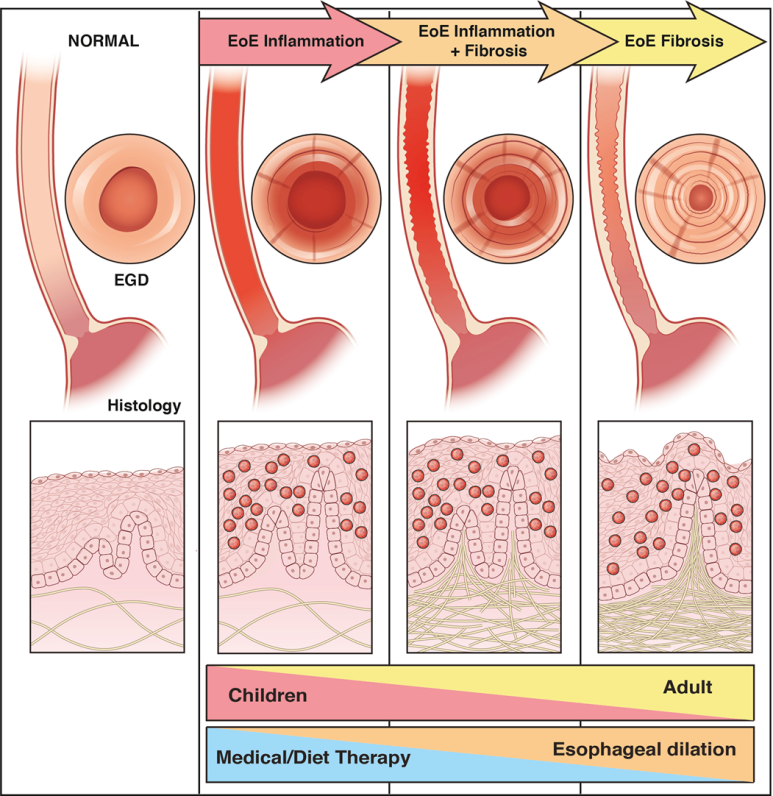

경과기 전에 말씀드렸다시피 먼저 호산구 식도염의 초기 증상은 염증 반응입니다. 이 염증 반응은 치료하지 않을 경우 esophageal remodling을 통해 내강이 좁아지고 기능 저하가 발생합니다. 하지만 항염증 요법을 시행할 경우, 호산구 식도염 질병의 진행 결과를 제한할 수 있다는 일부 보고가 발표되었습니다.이를 바탕으로 질병 발생 초기 또는 소아 청소년에서 발생한 호산구 식도염의 경우 약물치료 또는 식사치료를 할 수 있으나 이미 병변이 진행 중이고 섬유화가 진행된 경우 식도확장시술 외에는 다른 약물, 식생활료요법이 효과적이지 않습니다.